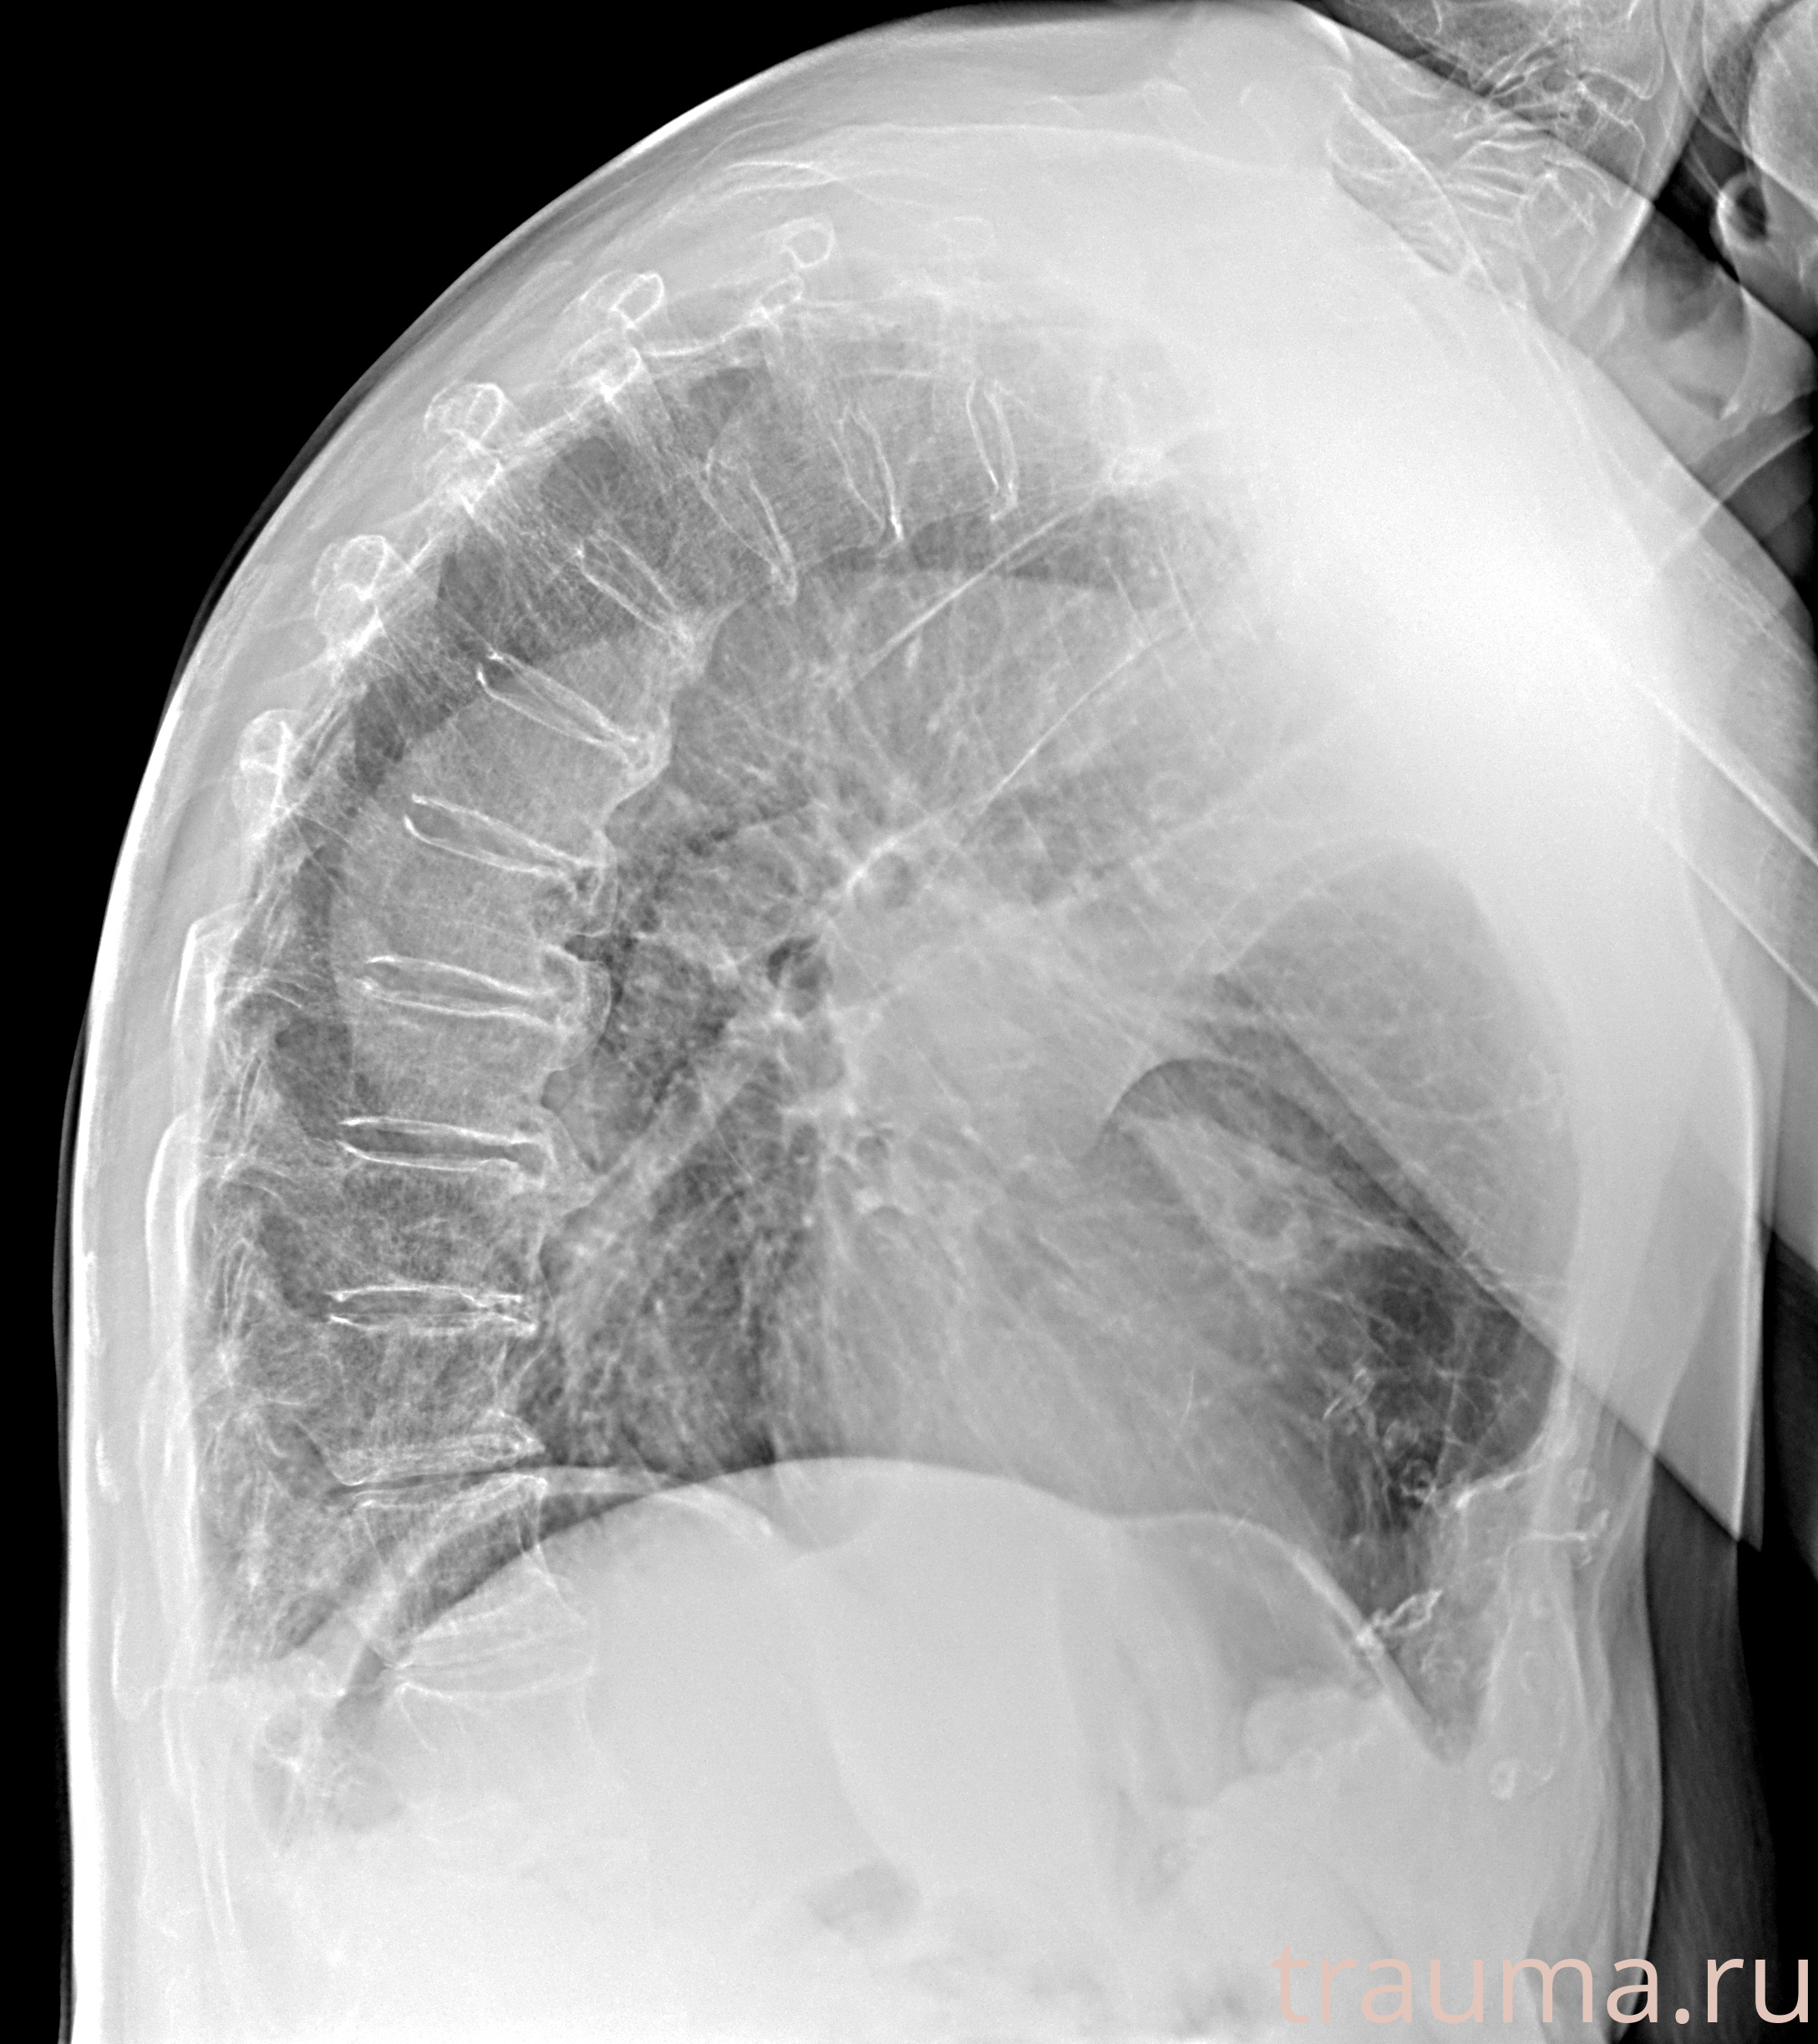

Рентген на дому: по вашему адресу приезжает врач-рентгенолог, травматолог-ортопед с мобильным рентгеновским аппаратом, проводит диагностику травмы или заболевания, делает необходимые рентгенограммы, дает рекомендации по дальнейшему лечению. Получить качественные снимки в домашних условиях возможно благодаря уникальной методике, разработанной МосРентген Центром для института  Склифосовского